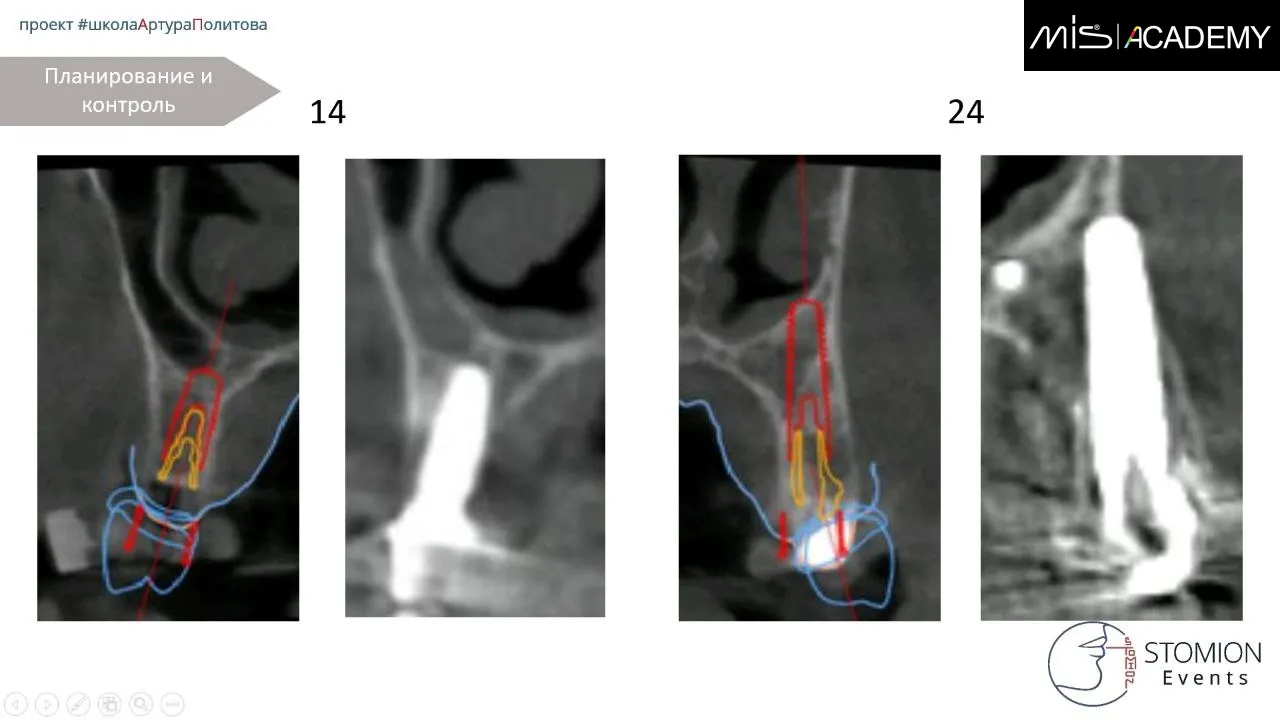

— Установка имплантатов MiS C1 в позициях 6-4-2-1-4-6.

— 1.6, 1.4, 2.4 — угловые МЮ,

— 1.2, 2.1 — коннекты,

— 2.6 — прямой МЮ.

— Колено угловых МЮ ориентированы либо строго по дуге, либо нёбно.